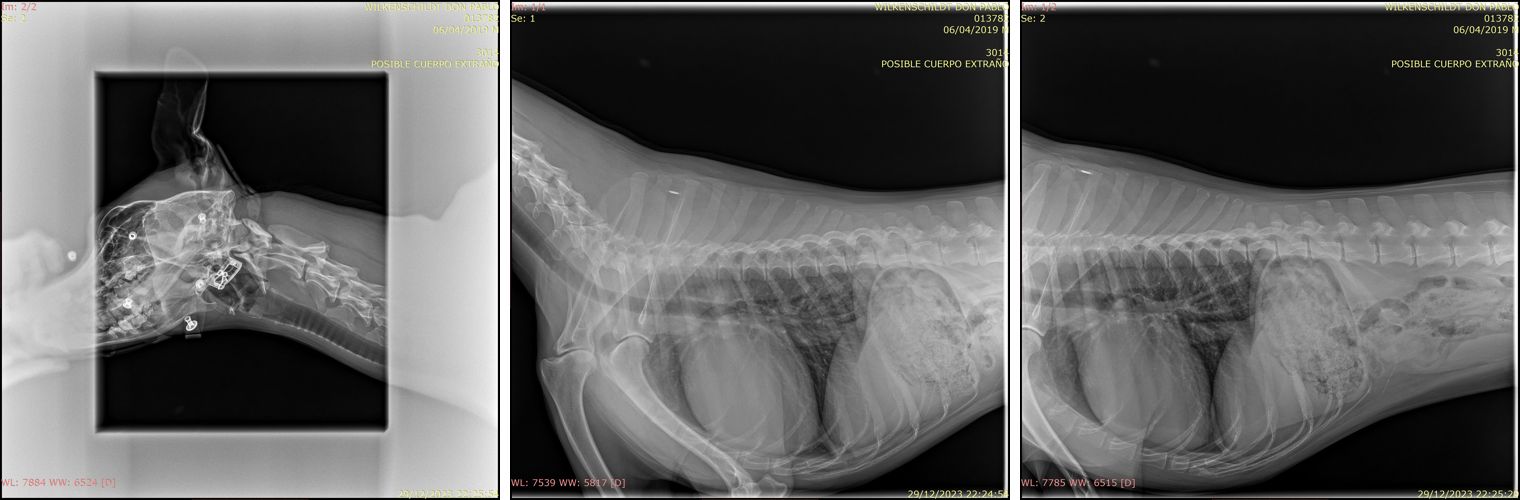

En dyrlæge gik straks i gang med et stetoskop og et termometer, mens en anden registrerede Don Pablo og ejerforholdet. Efter kort tid kom en anden dyrlæge. Vi fortalte om situationen, havde taget en tilsvarende kniv med, og hun tog Don Pablo med til røntgen uden protester fra ham.

- I må hjem og lede videre efter kniven, for Don Pablo har ikke nogen kniv i maven!

- Men jeg konstaterede, at han har noget uro i maven. Måske det skyldes nervøsitet…

Diskret opkrævede en anden derefter de 172 euro for urgente-konsultation og røntgen, som de havde orienteret om på forhånd.

På email modtog jeg dagen efter journal og røntgenbilleder